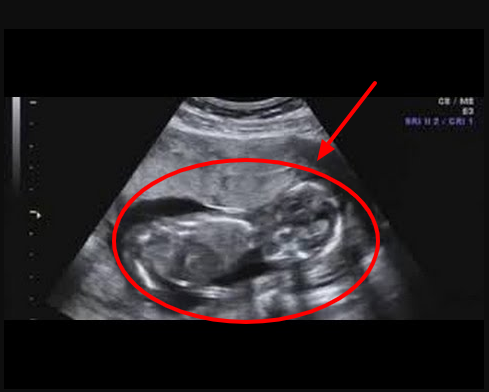

Namun, bagaimana perbedaan respon janin ketika diperdengarkan Al-Quran dan musik, bila dilihat melalui investigasi USG?

Sebuah penelitian yang dilakukan belakangan ini menemukan fakta bahwa terjadi perubahan aktifitas yang sangat luar biasa pada janin di dalam rahim ketika diperdengarkan bunyi lantunan Al-Quran.

Saat dilakukan investigasi USG (Ultrasonography) pada janin yang ibunya memutarkan rekaman ayat-ayat Al-Quran, terlihat bahwa si janin lebih hening seperti ikut mendengarkan dengan seksama lantunan ayat-ayat suci, sedangkan ketika diperdengarkan bunyi musik maka si janin menjadi lebih aktif bergerak.